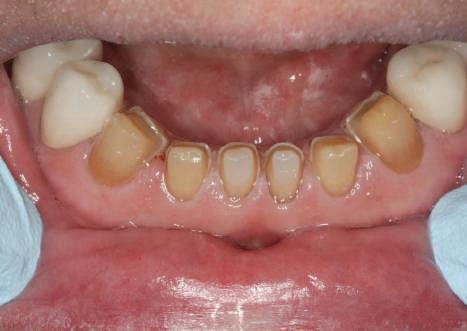

Reprepararea intraorală a bonturilor Acest pacient prezenta dentiţia maxilară compromisă, refuzând proteza mobilizabilă. Prin abordarea în etape, se menţin o parte din bonturile dentare naturale; s-a observat recesie în momentul amprentării pentru cel de-al doilea grup de implanturi.

Fig. 1 prezintă pacientul după inserarea primului set de bonturi implantare individualizate; dinţii naturali adiacenţi

sunt încă prezenţi pentru a susţine puntea provizorie.

Şapte luni mai târziu (fig. 2), acele bonturi individualizate din prima etapă au manifestat semne de recesie de 1-3mm. Atitudine: S-a decis reprepararea intraorală a tuturor bonturilor (fig. 3), astfel încât toate marginile bonturilor să fie la nivelul sau sub marginea gingivală (de notat că 1.1. şi 2.1. au fost submersaţi ulterior pentru a avea sprijin implantar deplin).

Deşi reprepararea a îmbunătăţit marcat estetica finală, a necesitat aplicarea şnurului de retracţie, amprente noi şi turnări noi.

Cazul (1): Reprepararea intraorală a bonturilor Figurile

1. Aspect după inserarea primului set de bonturi implantare individualizate.

2. După 7 luni, bonturile individualizate din prima etapă au prezentat recesie de 1-3mm.

3. Bonturile repreparate intraoral.